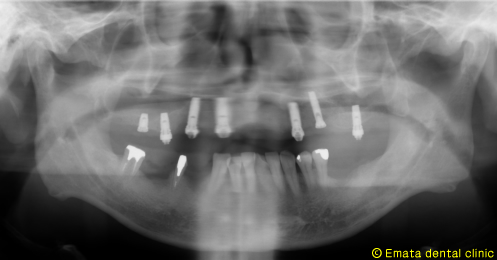

患者様は元々入れ歯をつかったことがありません。上顎6歯が歯周病が進行し残念ですがすべて抜歯です。年齢的(60歳)にも仕事上からも、総入れ歯は絶対いやだということで、All-on-4によりその日で固定式の仮歯を入れる手術をおこないました。

All-on-4は4本ではないかとおもいますが、骨の状態や対合歯が自分の歯なのでより確実性をもたせたいため5本で立ち上げ、2本はスリープさせました。

この症例のポイントは、ソケットリフト部位への即時負荷でしょう。アダプテーションテクニックにより40ニュートンの初期固定がえられました(専門的になってしまいましたね)。

治療後